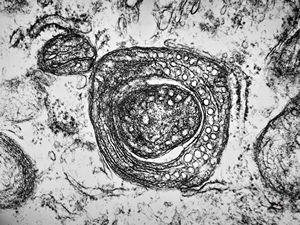

n. suralis - hypertrophic demyelinizing neuropathytoluidine-blue-stained semithin section

M, | hypertrophic (onion bulb) neuropathy accompanyingmultiple sclerosis

F,23y. | - n.suralis- hypertrophic demyelinizing neuropathy (onion bulbs)

F,12y. | hypertrophic (onion bulb) neuropathy - n.suralis